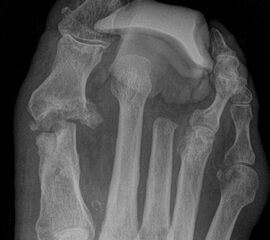

Exartikulationen im Großzehengrundgelenk bedingen bei Neuropathie häufig Druckulze­rationen am Metatarsalekopf (Abb. 6, 7). Wenn vertretbar, wird die Basis des Grundglieds mit den Sehnensansätzen erhalten, um chronische Druckprobleme zu vermeiden (Abb. 8). Im Falle einer Exartikulation ist dem Druck unter dem Metatarsale-I-Kopf große Aufmerksamkeit zu widmen. Durch eine Entfernung der Sesambeine und Abtragen von plantaren knöchernen Prominenzen kann die Auflagefläche vergrößert und damit der Druck reduziert werden. Postoperativ muss der Mittelfuß durch Einlagen in seinem Gewölbe breitflächig abgestützt werden (Abb. 9). Ansonsten resultiert ein Plattfuß mit Pronation und Abduktion.

Wir bevorzugen die Amputation im Mittelfußknochen gegenüber der Exartikulation im MTP Gelenk (Abb. 10): Ein Ulkus an dem Metatarsale I Stumpf ist durch stützende Einlage zu verhindern.

Tennisschlägerartige Umschneidung der Großzehe (Abb. 11). Das Metatarsale wird so osteotomiert, dass an der Medial- und Plantarseite keine Knochenkanten verbleiben (Abb. 12).